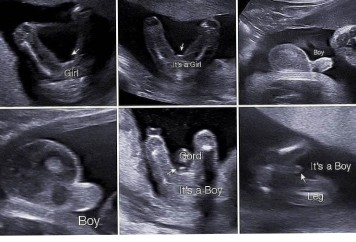

Ini bund aq punya gambarnya....smg membantu